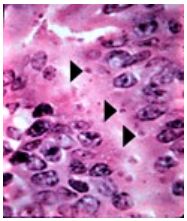

77.天竺鼠出現毛髮粗糙、發育不良、體重減輕、食慾不振及腹部稍微腫大等症狀,鏡下可見小腸病變 如箭頭所示,最可能由下列何種病原所引起?

(A)Cryptosporidium wrairi (B)Chlamydophila caviae (C)Eimeria caviae (D)Balantidium caviae